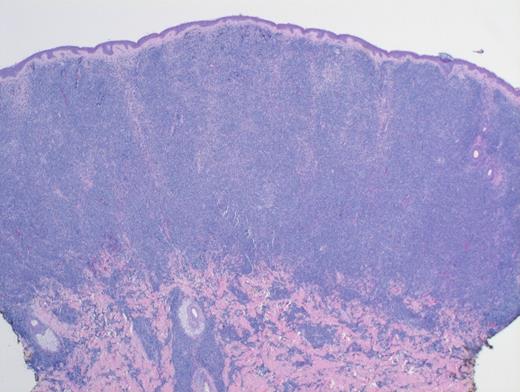

Low-Power H&E. Extensive, monotonous infiltrate composed of small- to medium-sized cells extending into the dermis. The epidermis is not involved (magnification x400).